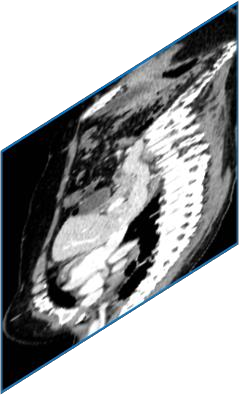

Due to the constraints of the imaging device and high cost in operation time, computer tomography (CT) scans are usually acquired with low intra-slice resolution. Improving the intra-slice resolution is beneficial to the disease diagnosis for both human experts and computer-aided systems. To this end, this paper builds a novel medical slice synthesis to increase the between-slice resolution. Considering that the ground-truth intermediate medical slices are always absent in clinical practice, we introduce the incremental cross-view mutual distillation strategy to accomplish this task in the self-supervised learning manner. Specifically, we model this problem from three different views: slice-wise interpolation from axial view and pixel-wise interpolation from coronal and sagittal views. Under this circumstance, the models learned from different views can distill valuable knowledge to guide the learning processes of each other. We can repeat this process to make the models synthesize intermediate slice data with increasing inter-slice resolution. To demonstrate the effectiveness of the proposed approach, we conduct comprehensive experiments on a large-scale CT dataset. Quantitative and qualitative comparison results show that our method outperforms state-of-the-art algorithms by clear margins.